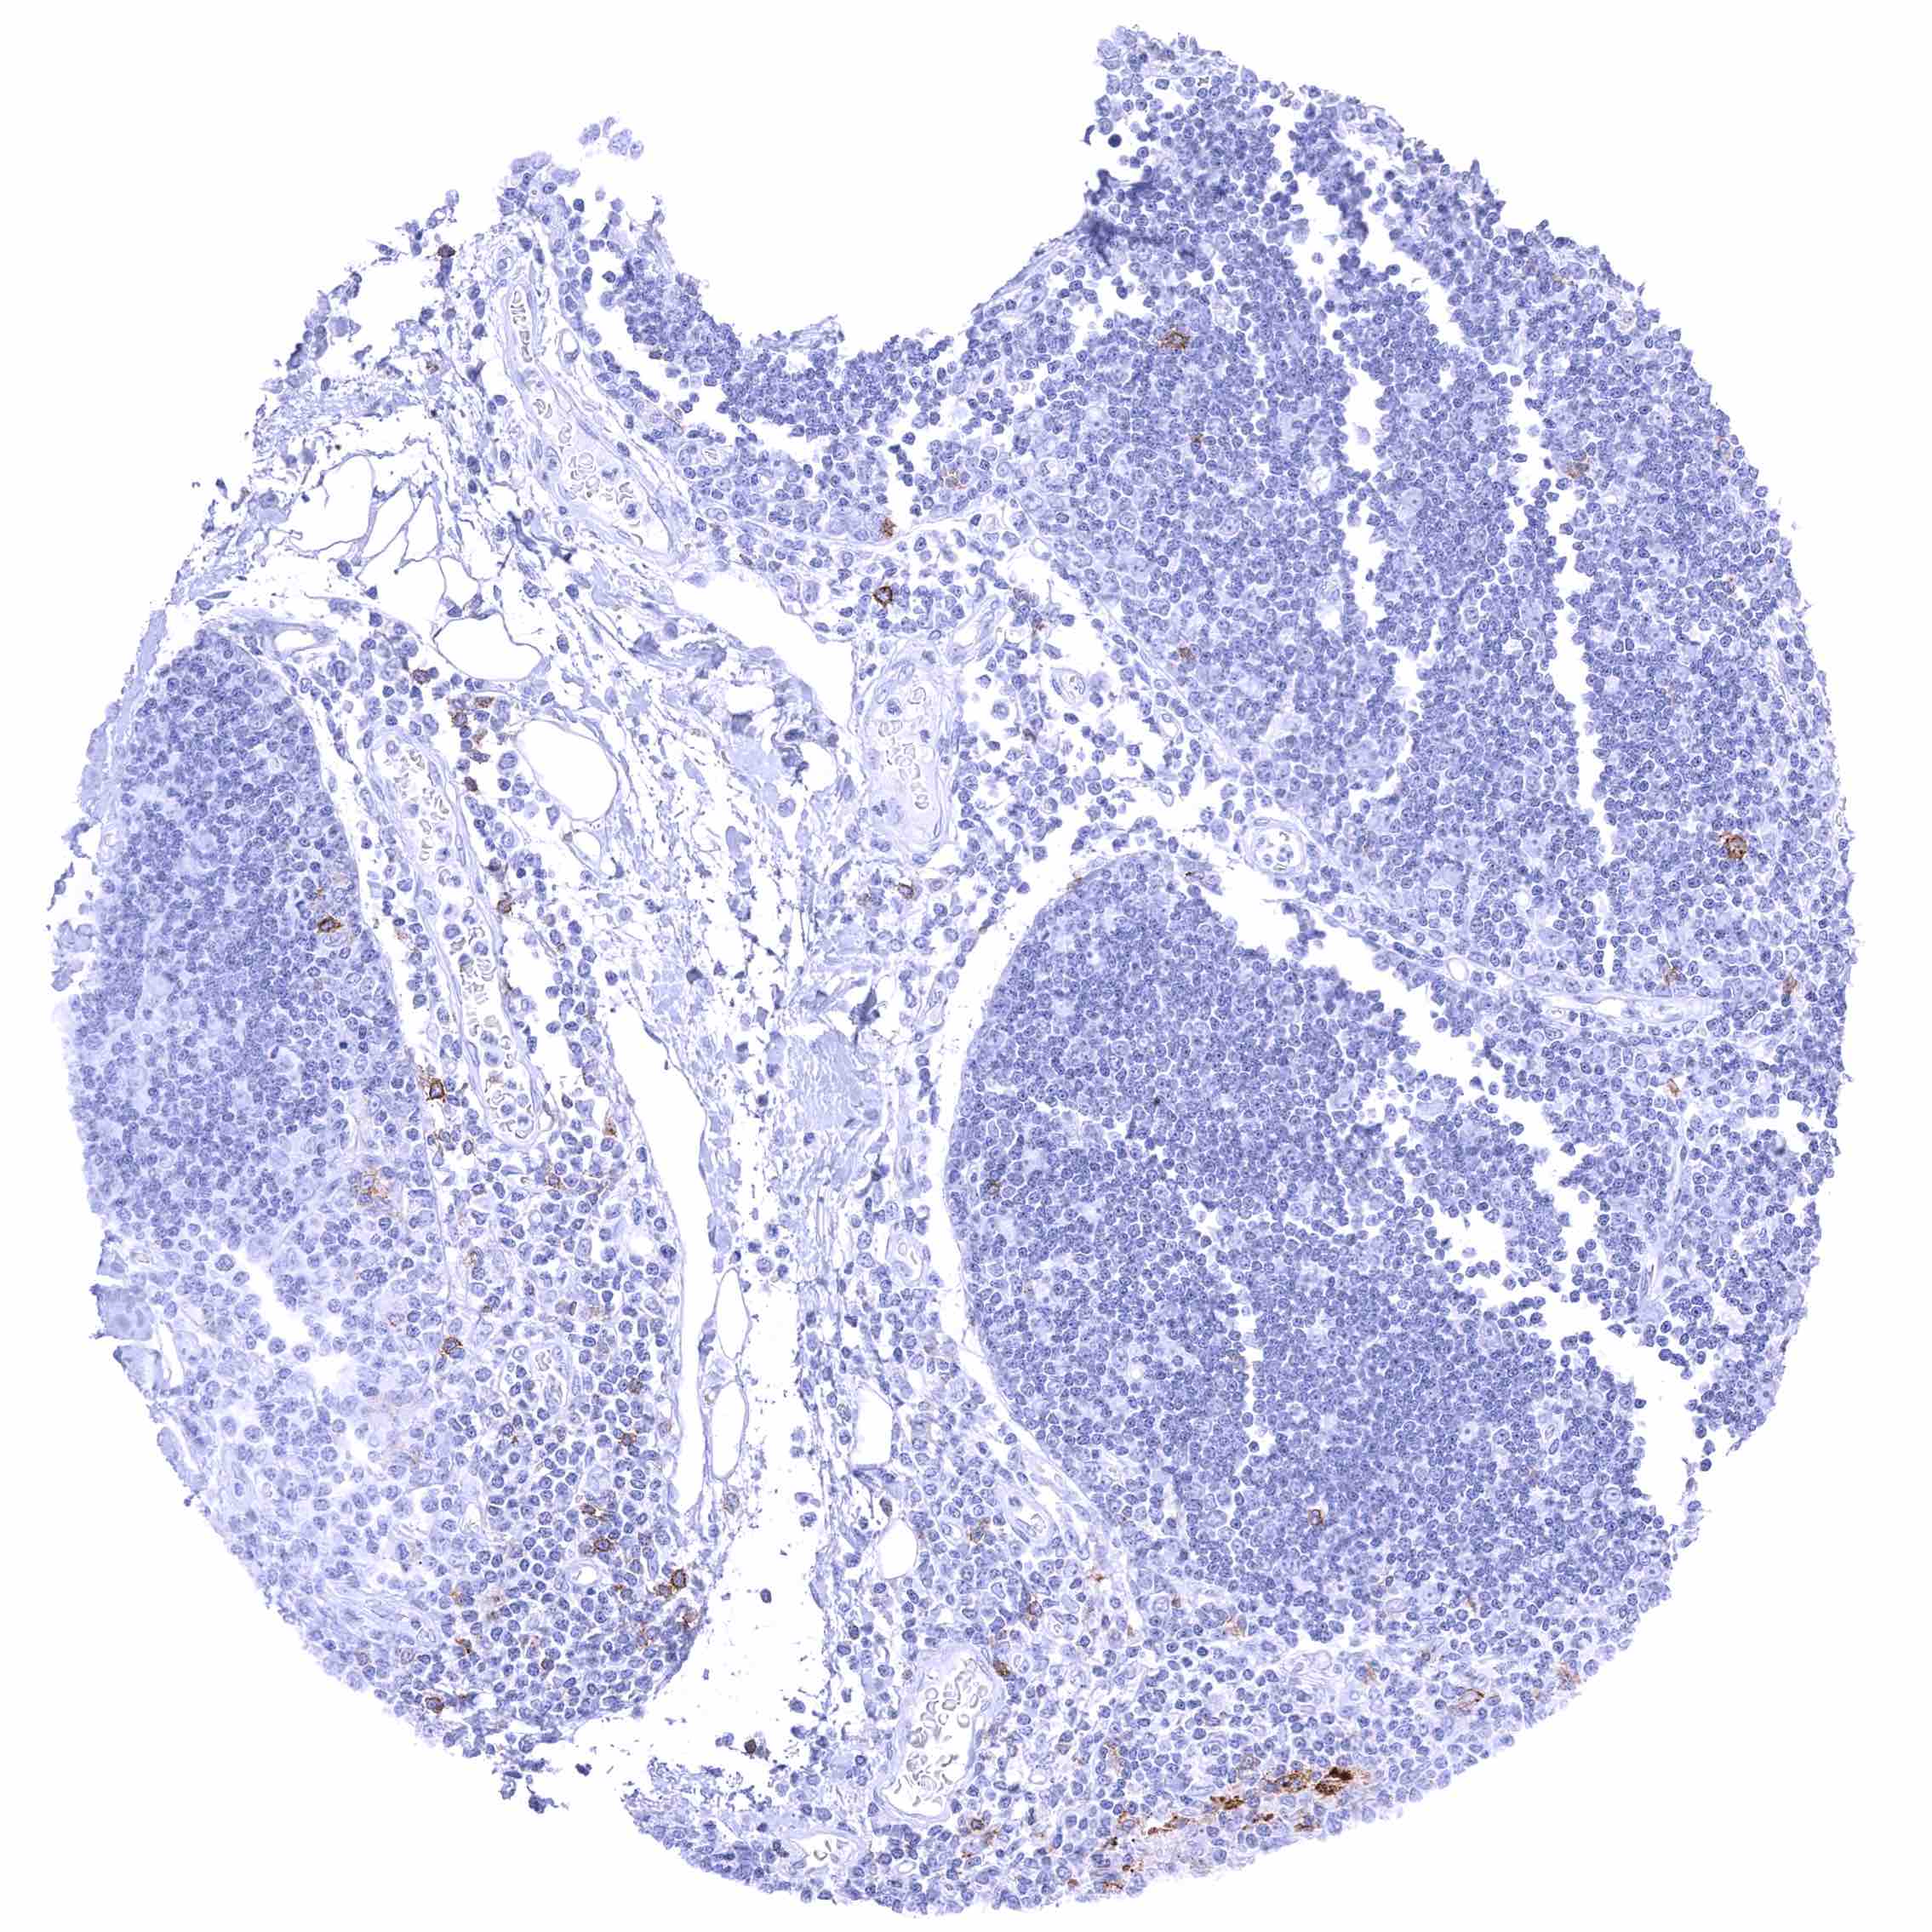

Lymph node – Membranous CD70 staining of variable intensity in subsets of cells (mostly lymphocytes). Most CD70 positive cells are interfollicular.

Tonsil – Membranous CD70 staining of variable intensity in subsets of cells (mostly lymphocytes). Most CD70 positive cells are interfollicular.